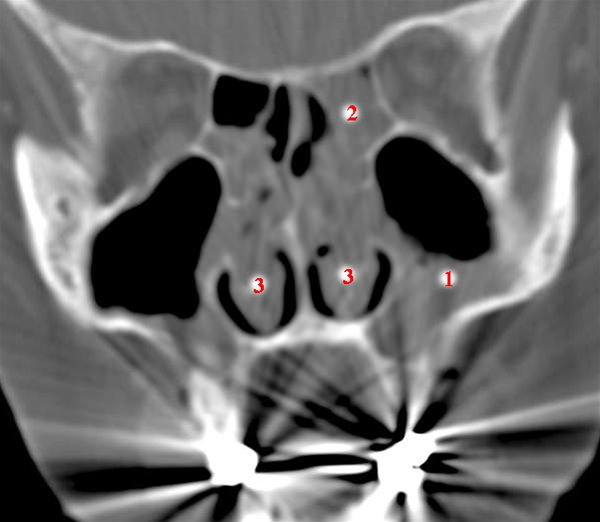

CT med coronale snit (højre side på billedet svarer til venstre på patienten).

Væske og sandsynlig dekliv slimhindefortykkelse i begge sinus maxillaris (kæbehuler), mest udtalt på venstre side (1).

Sløring af ethmoidalcellerne (sibenshuler)(2).

Diffus sløring af næsehulen, superiort for concha nasalis inferior (nederste del af næsehulen) (3)

Stribeartefakter fra tandfyldninger.